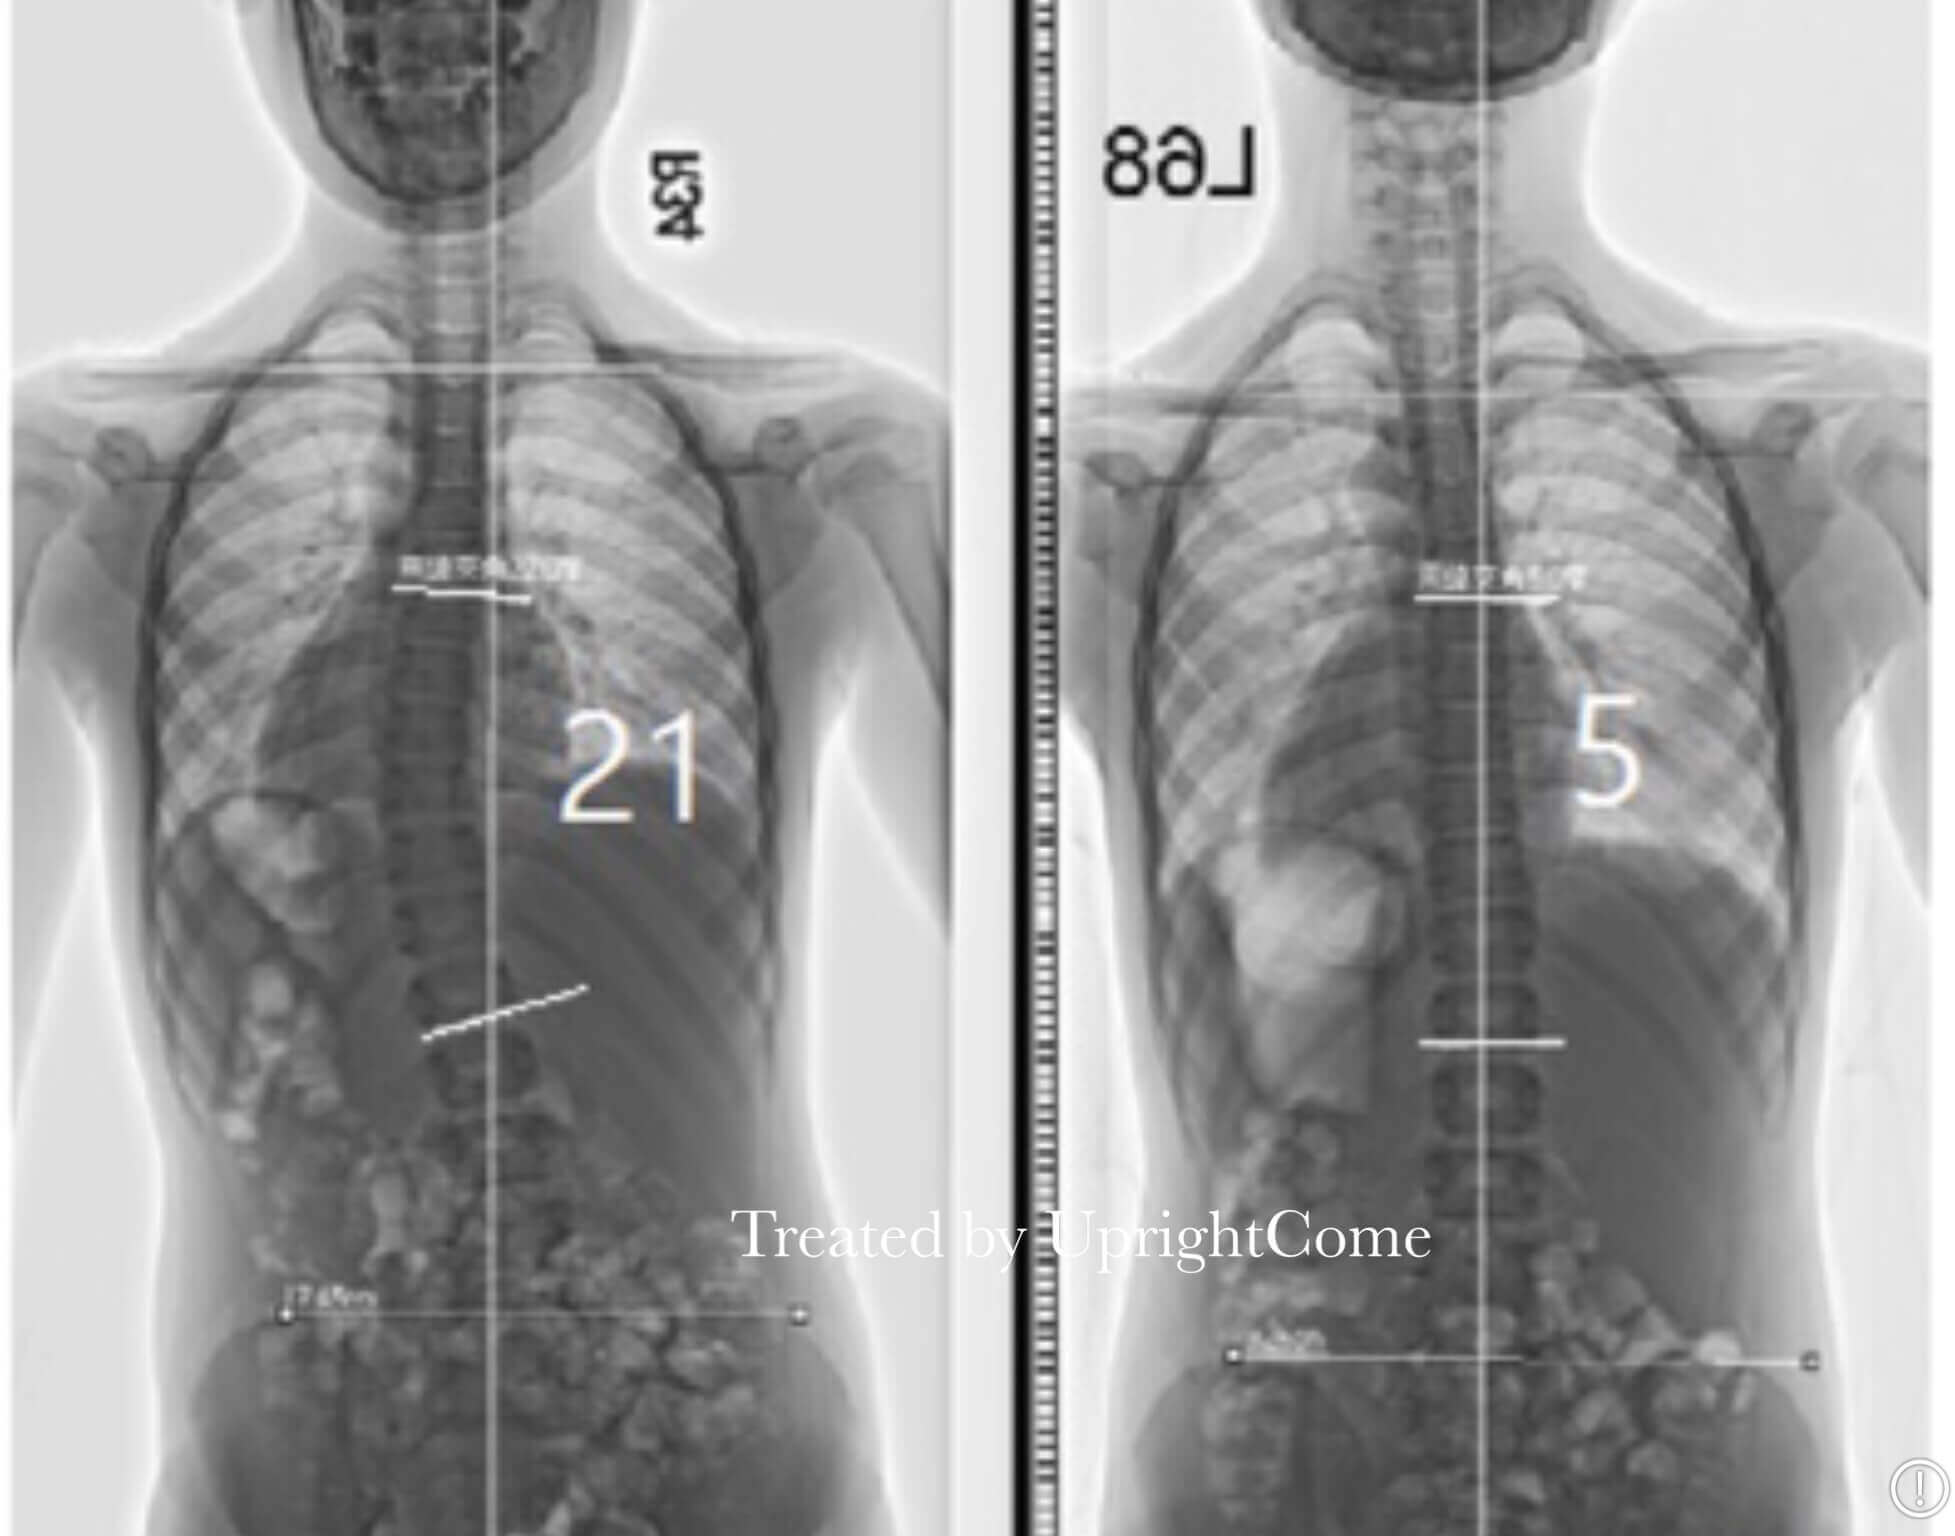

案例 5,14歲,33 度側彎

![脊椎側彎患者經過側彎矯正治療後,胸椎角度由33度減少到21度。]()